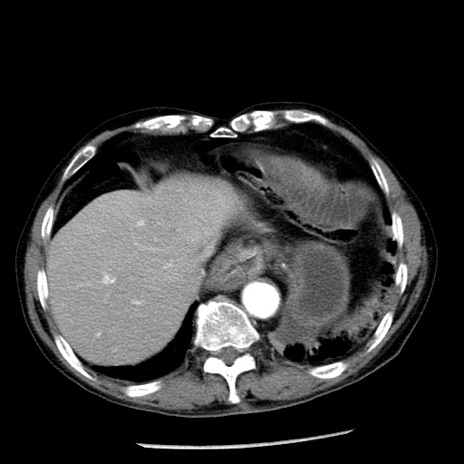

症例26(横断像)

【症例】80歳代男性

【主訴】嘔吐

【現病歴】昨晩2回嘔吐あり、今朝になっても嘔吐あり。来院。

【既往歴】胃潰瘍

【身体所見】意識清明、BT 37.6℃、BP 166/95mmHg、HR 100bpm、SpO2 97%、腹部:平坦・軟、腸蠕動音聴取良好、圧痛なし。

【データ】WBC 21900、CRP 1.46